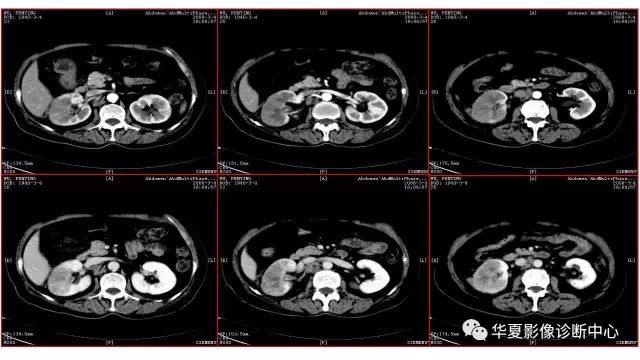

【病例】不典型肾透明细胞癌1例CT影像表现

【病例】肾透明细胞癌1例CT影像表现